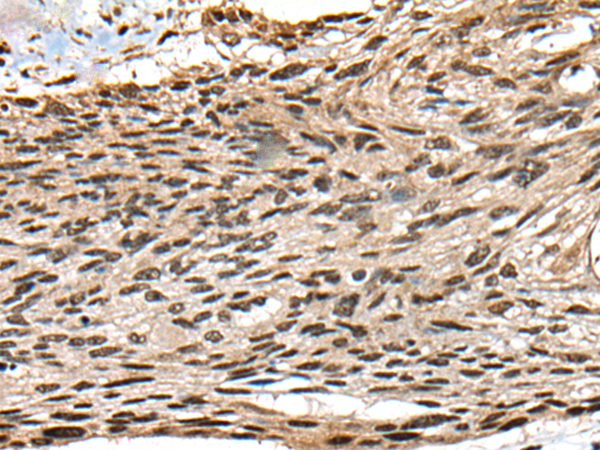

CTSF Protein, a thiol protease, participates in intracellular protein degradation and turnover. Its association with tumor invasion and metastasis suggests potential involvement in critical cellular processes related to cancer progression. CTSF Protein, Human (His) is the recombinant human-derived CTSF protein, expressed by E. coli , with N-His labeled tag.